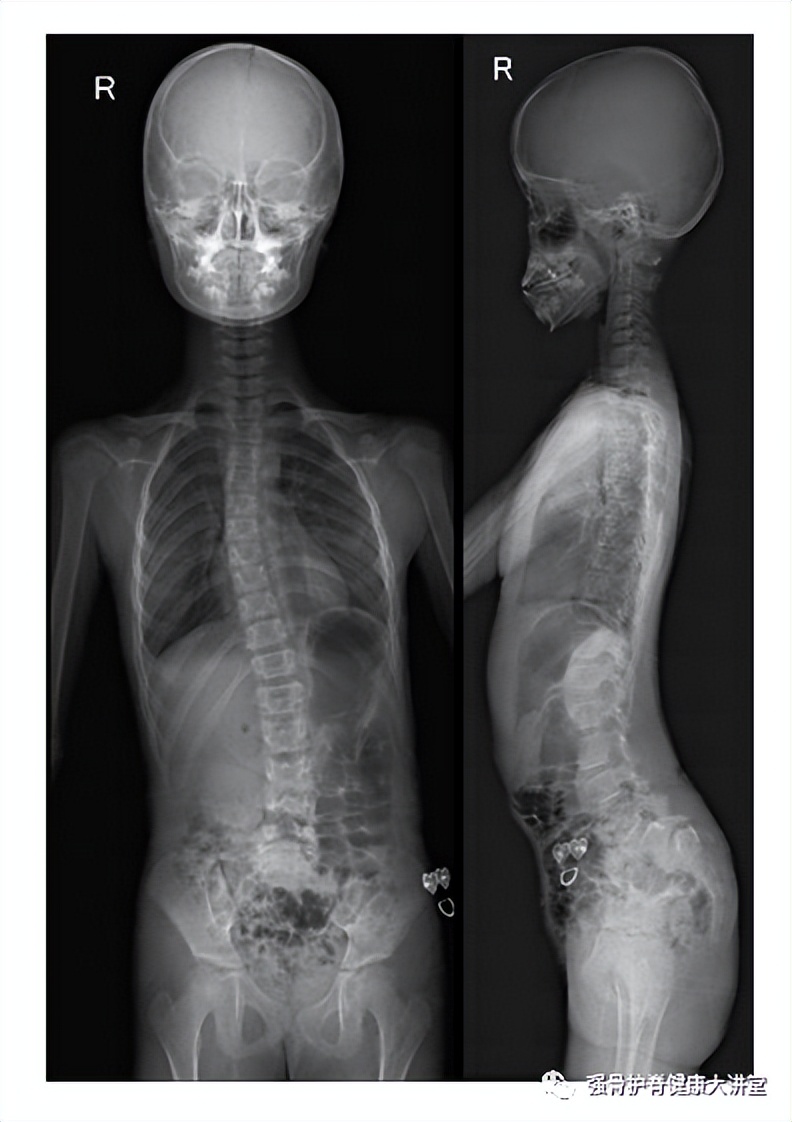

A 12yearold girl with severe congenital scoliosis treated by Scoliosis Caused By Heavy Backpacks Neither does playing sports, though some should be avoided if you have. It’s also very common for parents to ask if bad posture or heavy backpacks could have caused their child’s scoliosis. Back pains caused by heavy backpacks are usually temporary. Backpacks should be worn using both straps. While heavy backpacks may cause back, shoulder, and neck pain, they don’t. Scoliosis Caused By Heavy Backpacks.